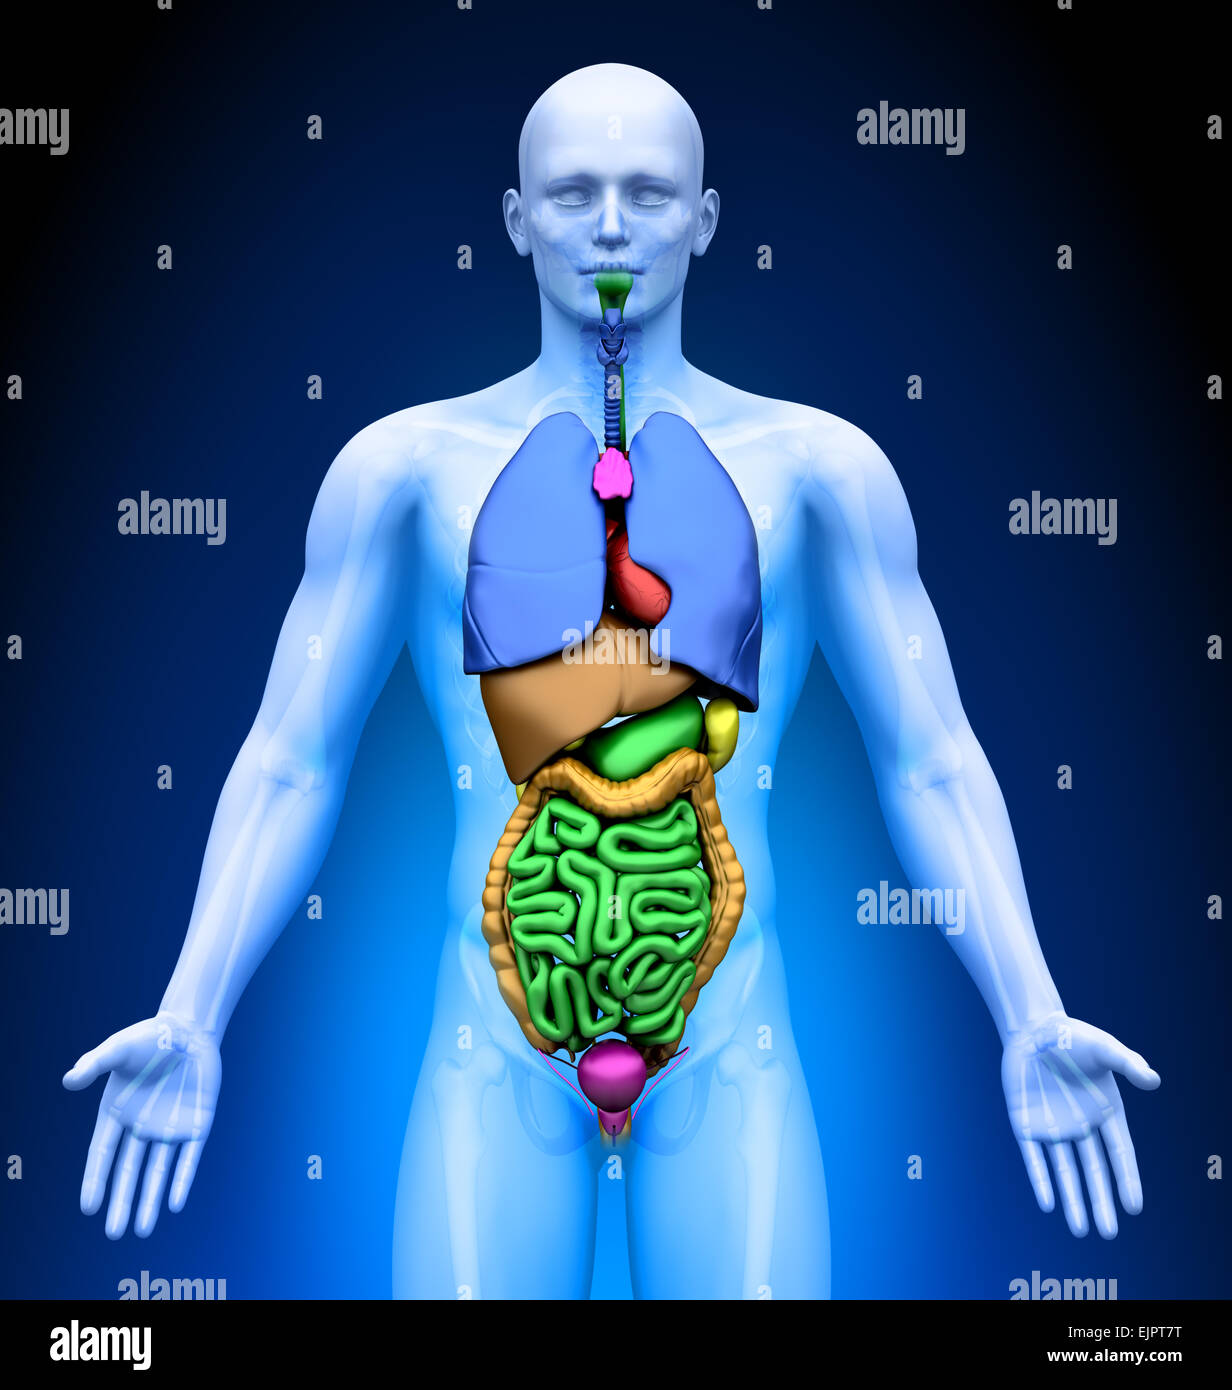

Male Internal Organs Anatomy Stock Photo Alamy

https://c8.alamy.com/comp/EJPT7T/male-internal-organs-anatomy-EJPT7T.jpg

Male Internal Organs Anatomy Stock Photo Alamy